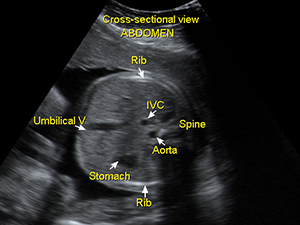

Cross-sectional view of the fetal abdomen